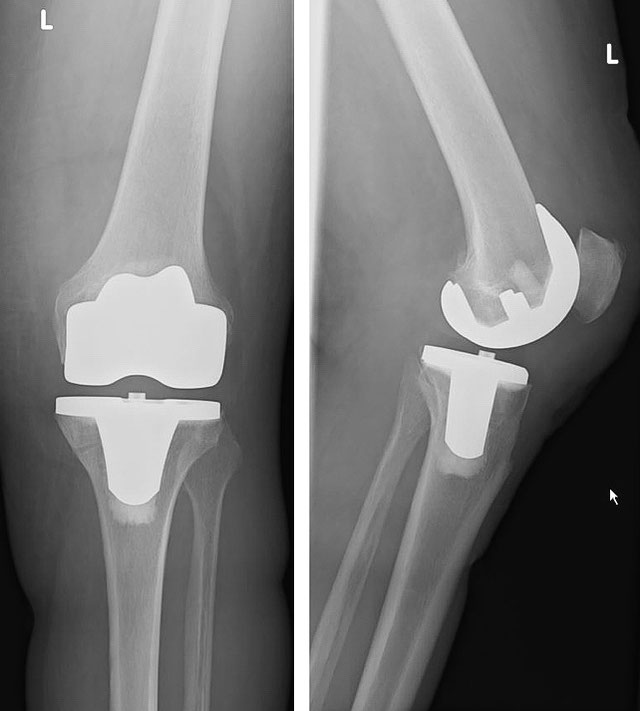

Knieendoprothese

KnieTotalprothese Orthopädie Sonnenhof Bern

Diagnostik und Therapieverfahren bei Kniearthrose EndoProthetikZentrum Schwaben

KnieTeilprothese OP und Nachbehandlung Sportklinik Ravensburg